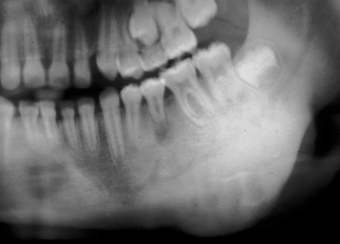

Grande cisto dentígero envolvendo ramo mandibular, essa lesão radiograficamente

poderia ser diagnosticada como uma ceratocisto odontogênico ou ameloblastoma unicístico.